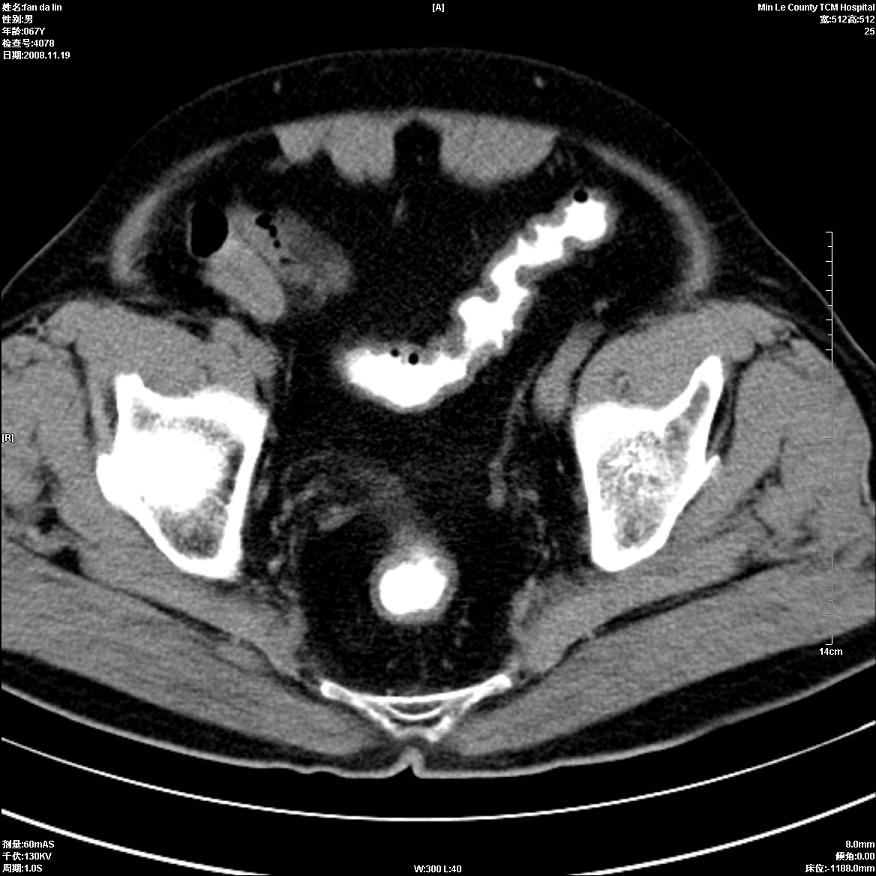

标题: CT16698:M67Y,看看直肠下端是不是病变 [打印本页]

标题: CT16698:M67Y,看看直肠下端是不是病变

粘膜皱壁,不除外内痔

直肠及乙状结肠管壁均增厚,考虑炎症.

直乙交界处肠壁不规则增厚,还是做个肠镜吧

只是肠壁局限性增厚,但难说明问题。